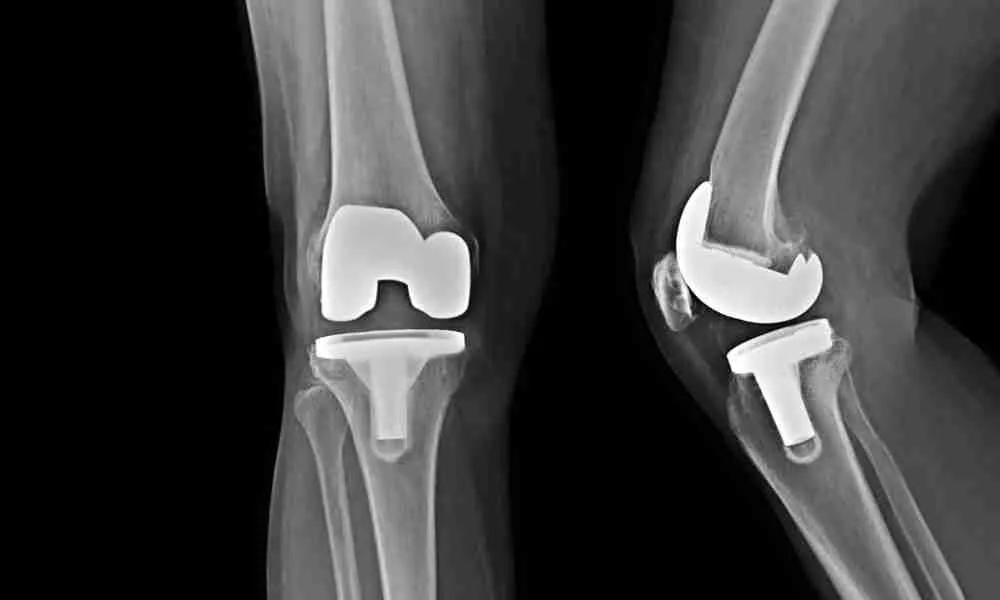

Total Joint Replacement

Medicare provides coverage for hospital stays and surgeries through different parts of the program. Part A covers inpatient hospital care, which includes expenses for the room, meals, and nursing services. Meanwhile, Part B covers medically necessary surgeries, including the surgeon’s fees and anesthesia.

Medicare covers surgeries deemed medically necessary, such as hip, knee, and shoulder replacements. Check with your provider for specific details.